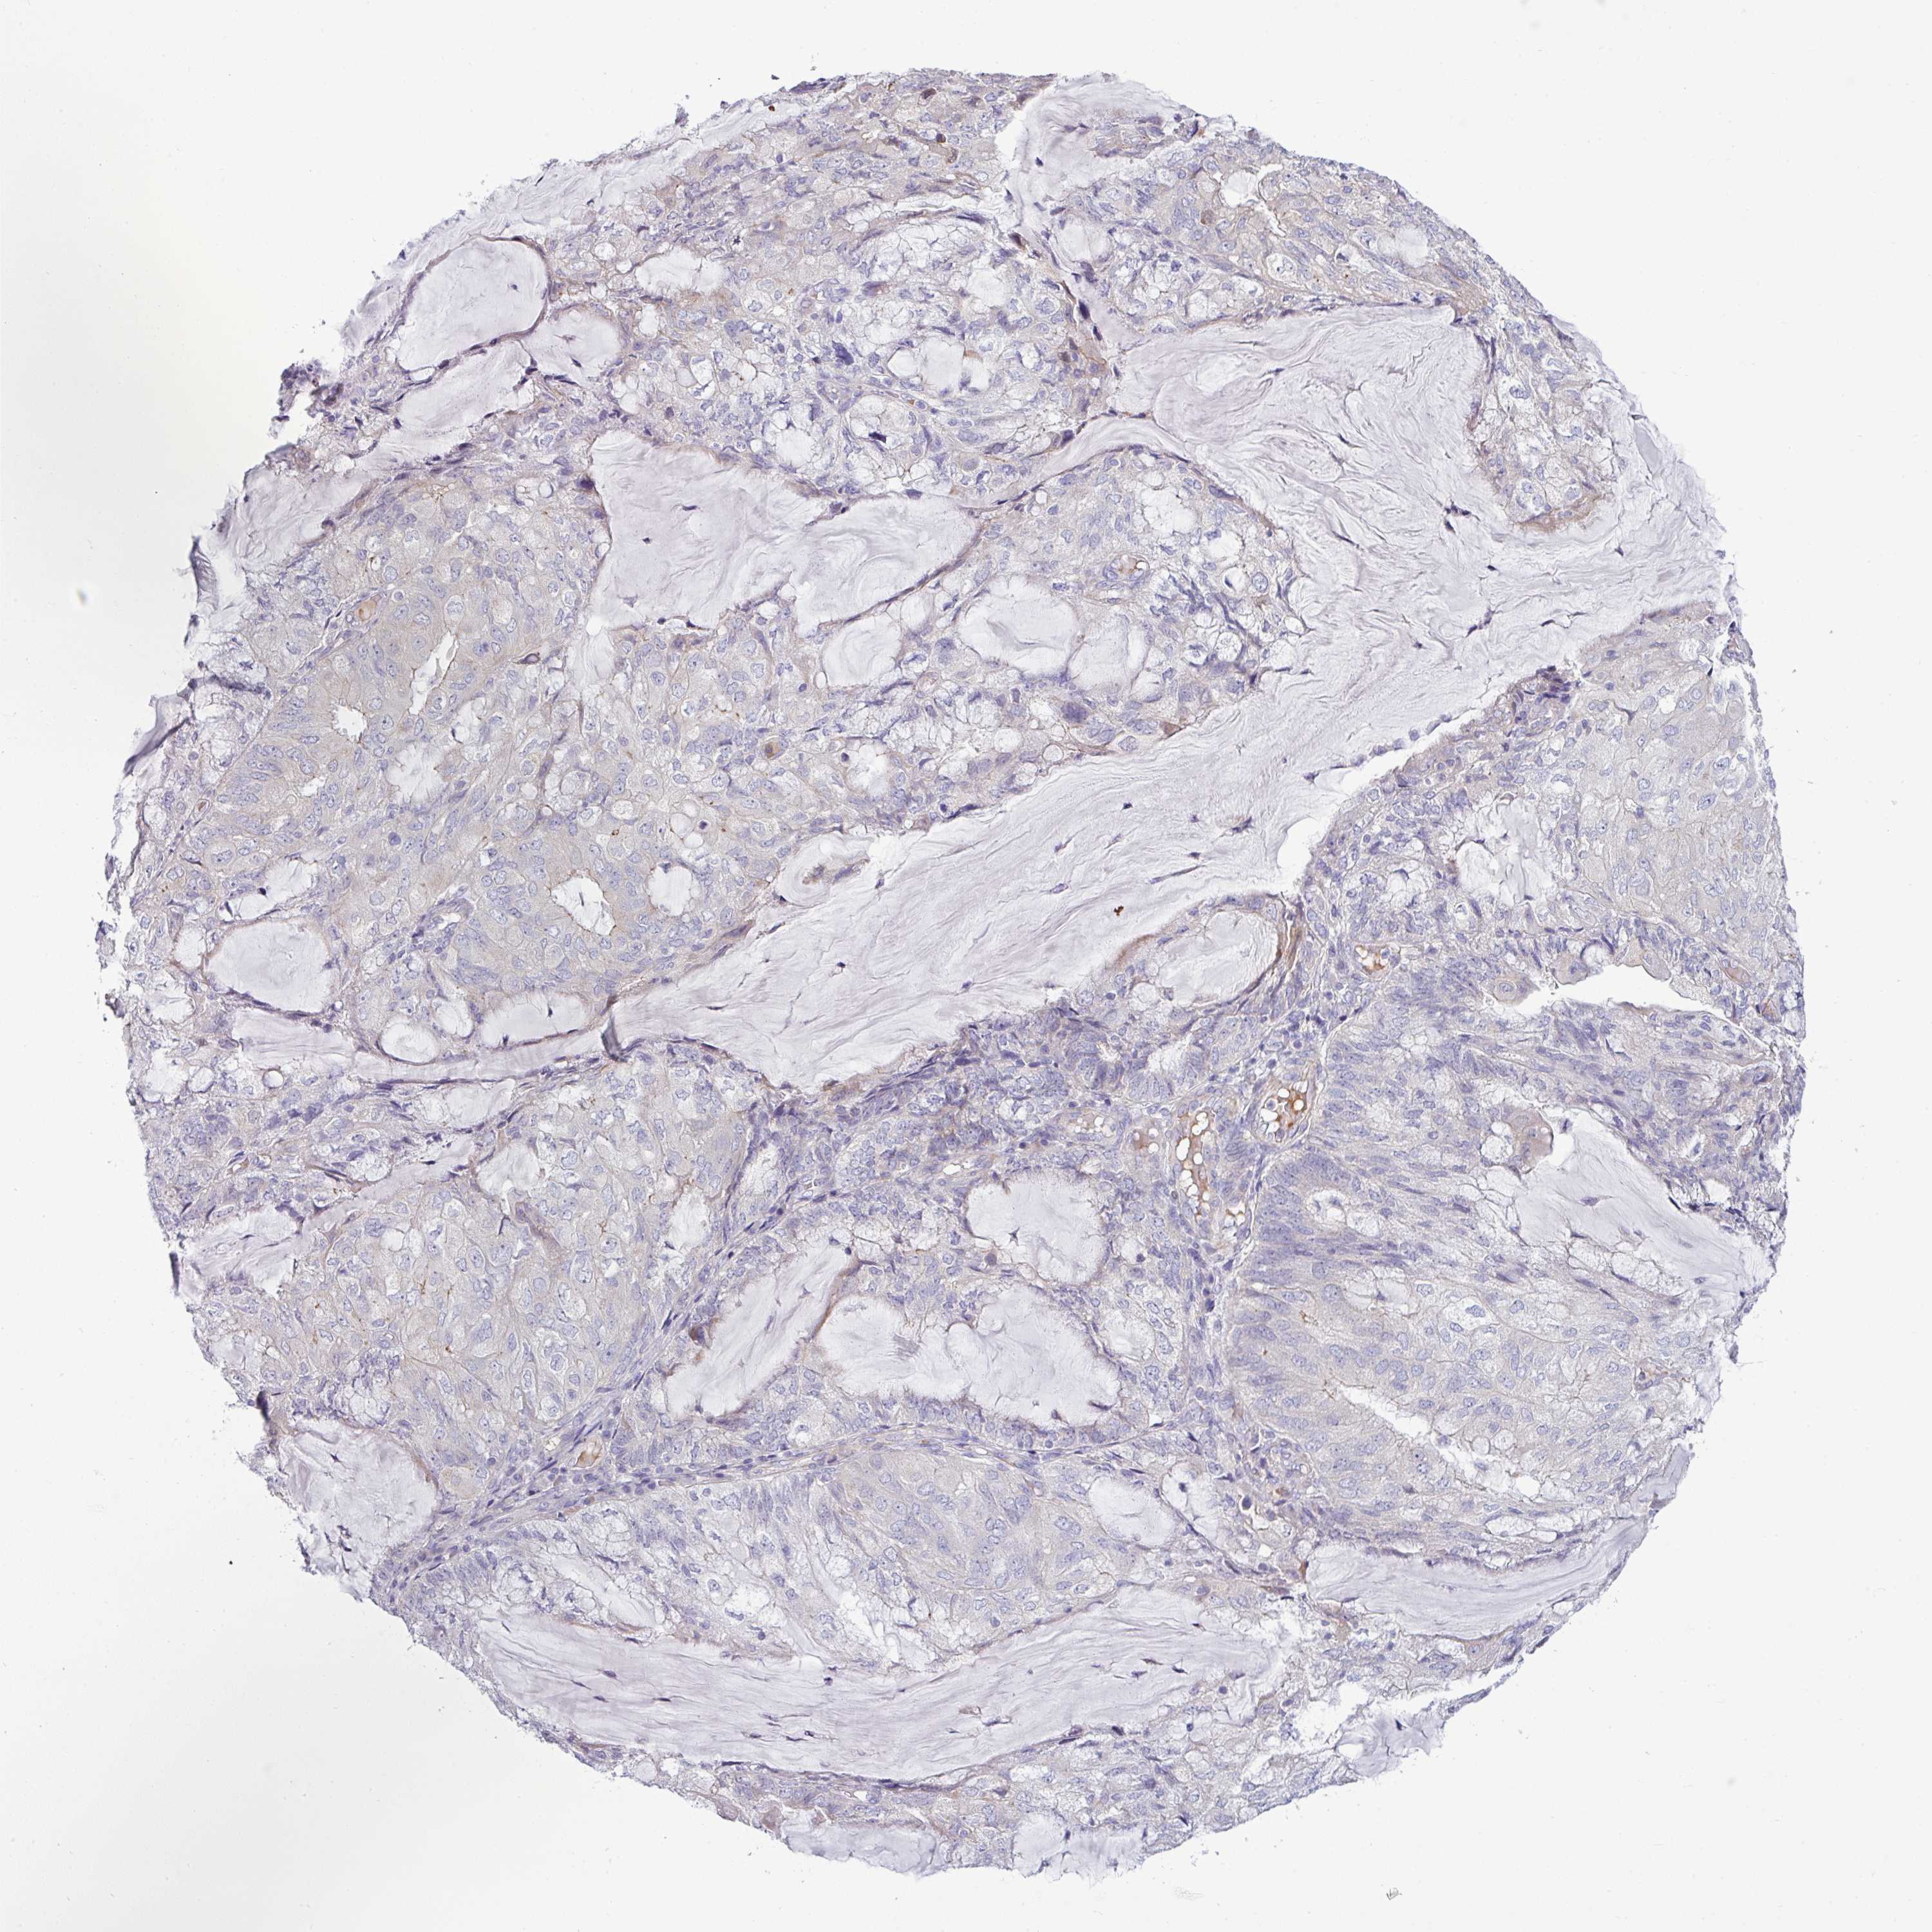

ENDOMETRIAL CANCER - Protein expressioni

A mouse-over function shows sample information and annotation data. Click on an image to view it in a full screen mode. Samples can be filtered based on level of antibody staining by selecting one or several of the following categories: high, medium, low and not detected. The assay and annotation is described here.

Note that samples used for immunohistochemistry by the Human Protein Atlas do not correspond to samples in the TCGA dataset.

Antibody stainingi

Antibody staining in the annotated cell types in the current human tissue is reported as not detected, low, medium, or high, based on conventional immunohistochemistry profiling in selected tissues. This score is based on the combination of the staining intensity and fraction of stained cells.

Each image is clickable and will lead to virtual microscopy that enables deeper exploration of all samples and also displays staining intensity scores, fraction scores and subcellular localization as well as patient and tissue information for each sample.

Antibody HPA049317

Staining

High

Medium

Low

Not detected

Intensity

Strong

Moderate

Weak

Negative

Quantity

>75%

75%-25%

<25%

None

Location

Nuclear

Cytoplasmic/membranous

Cytoplasmic/membranous,nuclear

Adenocarcinoma, NOS